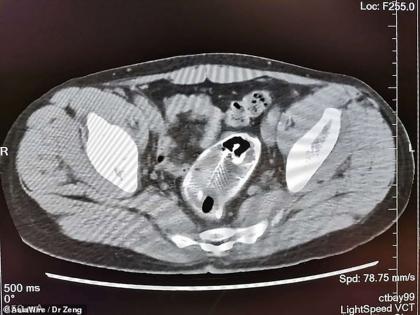

या व्यक्तीचं वय 30 आहे. झाओकिंग पीपल्स हॉस्पिटलमध्ये त्याचं ऑपरेशन करण्यात आलं. यात 16 इंच लांब एक पूर्ण मासा बाहेर काढण्यात आला. व्यक्तीच्या उत्तराने डॉक्टर हैराण आहेत. ते म्हणतात की, कोणतीही व्यक्ती कपड्यांविना माशावर का बसेल? जर तो बसला तरी मासा त्याच्या शरीरात शिरत आहे हे त्याला समजलं कसं नाही. ही घटना चीनमधील सोशल मीडियावर व्हायरल झाली आहे.

डॉक्टरांनी सर्जिकल ऑपरेशन करून मासा काढला. त्यांनी सांगितले की, हा मासा त्याच्या गदद्वारात अनेक दिवसांपासून होता. जर आणखी थोडा उशीर झाला असता तर गंभीर समस्या झाली असती. मासा आतल्या आत सडू लागला होता. त्यामुळे रेक्टमसोबतच पोटातली इन्फेक्शन पसरलं होतं. सध्या ही व्यक्ती ठिक आहे.